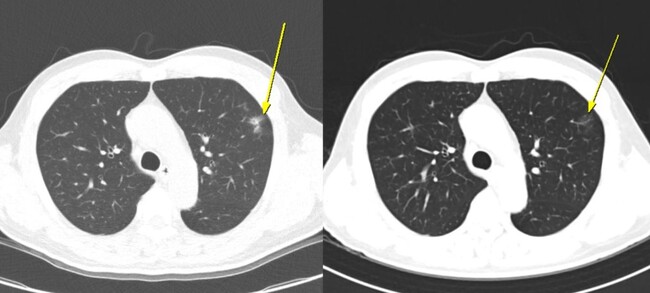

치료 반응률에서도 차이가 분명했다. 무증상 영상군의 객관적반응률(ORR)은 41.7%, 질병조절률(DCR)은 100%로 가장 높았으며, 증상군은 각각 26.8%와 92.9%, 무이상반응군은 13.8%와 60.0%로 뒤를 이었다. 이는 환자가 증상을 느끼지 않더라도 CT에서 보이는 경미한 변화가 치료반응이 좋은 환자를 조기에 식별하는 중요한 단서가 될 수 있음을 시사한다. AteBeva 치료 3개월째 시행한 저선량 흉부 CT(왼쪽)에서 폐 주변부에 미세 염증성 음영이 나타났으나, 6개월째 CT(오른쪽)에서는 자연적으로 소실되는 양상을 보였다. 치료는 지속됐으며, 이후 부분 관해(PR)를 달성했고 총 19.7개월간 무진행 생존(PFS)을 유지했다.